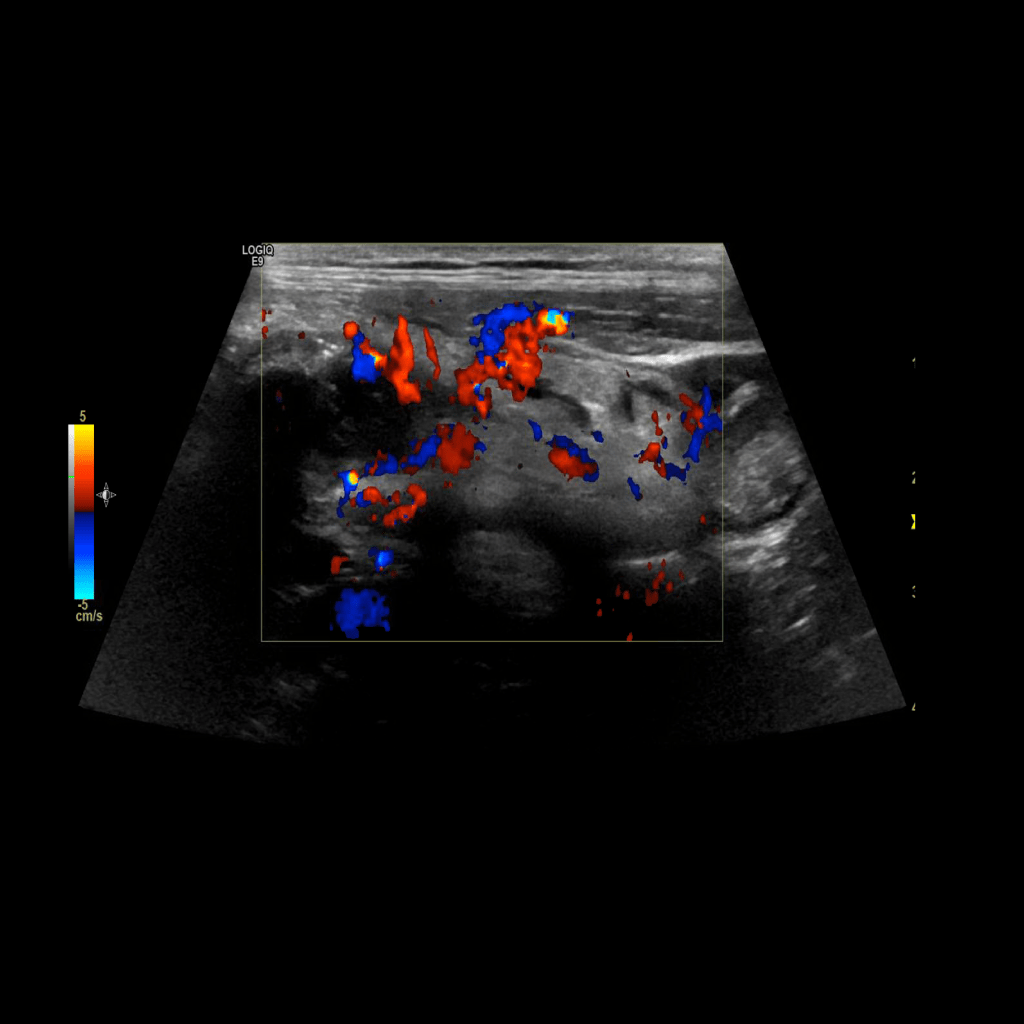

Appendicitis 13

Acute appendicitis @ 1 cm with L2-9mhz and L6-24mhz transducer GE Logiq e10.